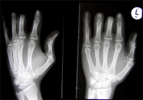

Lengthening all 3 amputated fingers with satisfied patient

Final Result